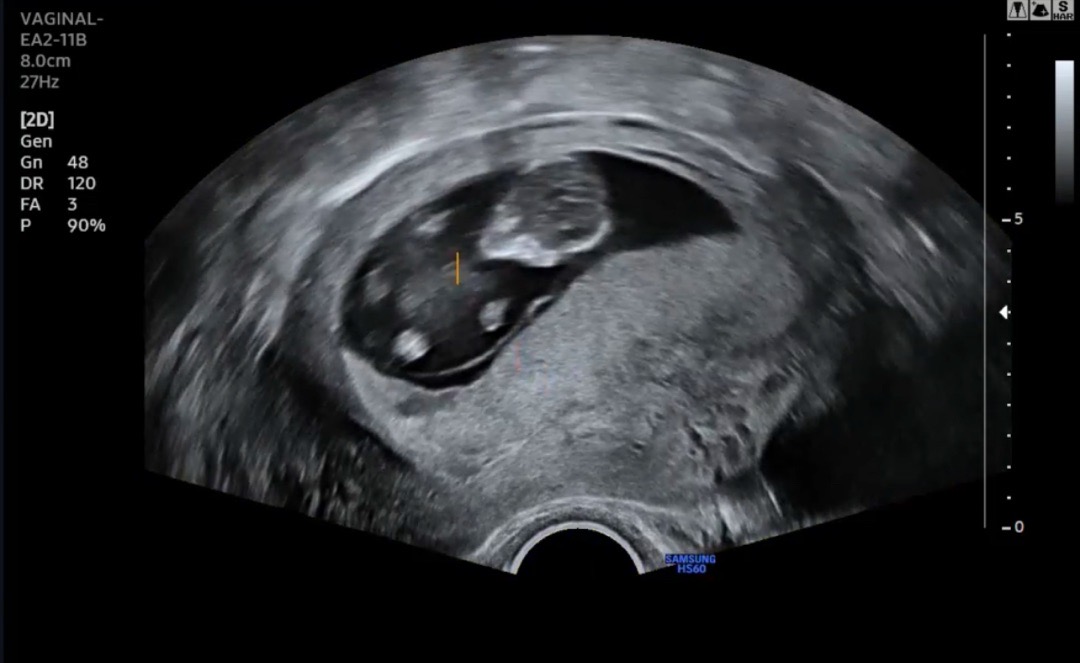

11주차 정밀검진

CRL 4.81cm로 훌쩍 크고, 코뼈 확인. NT도 0.12cm로 무사 통과. 니프티결과도 저위험군😊 딸❤️으로 결과지 확인하고 왔네요! 이제 팔다리도 보이고 귀여워요ㅎ